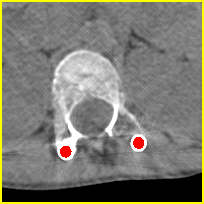

Visual comparison. As shown in Fig. 5, metallic implants such as spinal rods and hip prosthesis cause severe streaky artifacts and metal shadows, which obscure bone structures around them. cGan-CT cannot recover image intensity correctly for both cases. Sinogram domain or dual-domain methods perform much better than cGan-CT. LI, NMAR, and CNNMAR introduce strong secondary artifacts and distort the whole images. In NMAR images, there are fake bone structures around the metals, which is related to segmentation error in the prior image from strong metal artifacts. The segmentation error is also visible in NMAR sinogram. CNNMAR cannot restore the correct bone structures between rods in case 1. The tissues around the metals are over-smoothed in DuDoNet because LI sinogram and image are used as inputs, and the missing information cannot be inferred later. Our model retains more structural information than DuDoNet and generates anatomically more faithful artifact-reduced images.

Visual comparison. Fig. 7 shows two clinical CT images with metal artifacts. Case 1 is with moderate metal artifacts. cGan-CT does not suppress the artifacts completely and generates some fake details. LI, NMAR, CNN-MAR remove all the artifacts but introduce new streak artifacts, which is caused by the discontinuity in the corrected sinogram. DuDoNet outputs over-smoothed sinogram, which leads to blurred tissues close to the metal implants, such as muscle and bone. Only our model can provide realistic enhanced sinogram and remove the artifacts while retaining the structure of nearby tissues. Case 2 is very challenging as the rods bring strong metal shadows and bright artifacts around the vertebra. cGan-CT recovers the shape of vertebra but changes the overall image intensity. Other sinogram inpainting methods fail as the soft tissue and bone near the rods are heavily distorted. Our model removes part of the dark bands and reproduces correct anatomical structures around the rods.